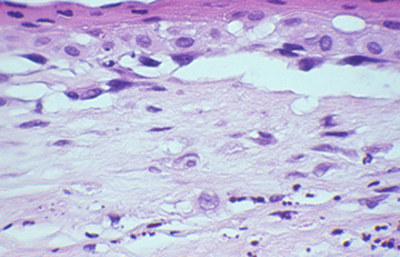

Cuando el examen patológico se realiza en cortes de tejido corneal procesados en parafina, (biopsias y discos de córnea de queratoplastias) las coloraciones que empleamos usualmente son la coloración de Hematoxilina-Eosina (Figura 49), el Blanco de Calcofluor. (Figura 50), la de PAS (Figura 51 y 52). De nuevo, la consideración de que una infección corneal puede ser causada por Acantamoebas es la condición indispensable en el diagnóstico diferencial para llegar a su diagnóstico

Fig. 47 Giemsa, Original x400

Fig. 48 Giemsa, Original x400

Fig. 49 H-E, Original x160

Fig. 50 CW, Original x160

Fig. 51 PAS, Original x160

Fig. 52 PAS, Original x160